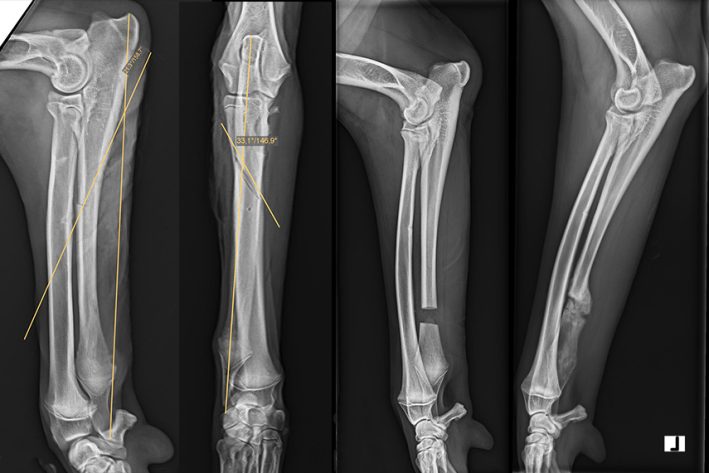

Distale Ulnaostektomie

Distale Ulnaostektomie Vermessungsröntgen, pre und postoperativ